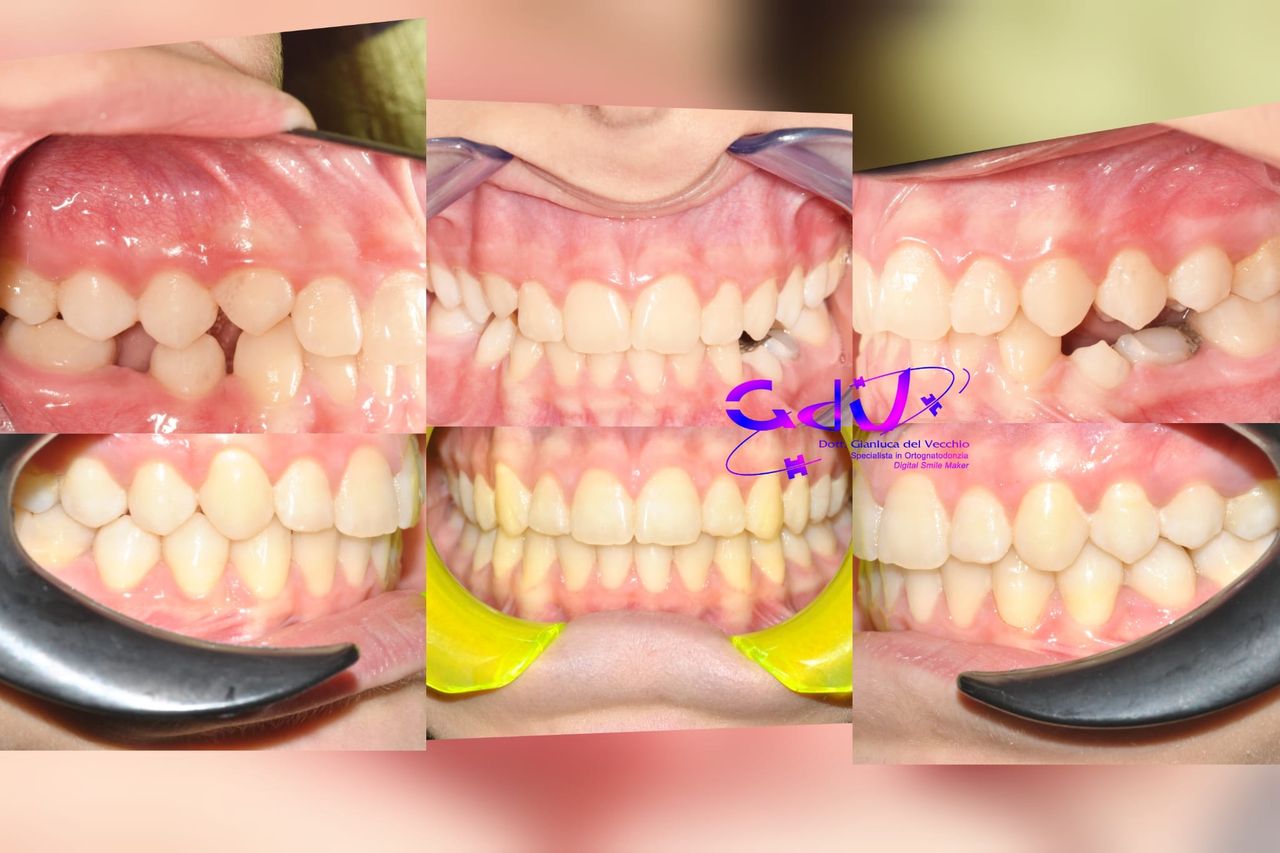

Il dottor Gianluca del Vecchio si occupa esclusivamente di ortognatodonzia, grazie anche alla collaborazione multidisciplinare di una équipe davvero entusiasmante e all’utilizzo di strumenti diagnostici e terapeutici all’avanguardia in ortognatodonzia. Particolare è la sua capacità di condurre i giovani pazienti ad affrontare, nella massima sicurezza emotiva e clinica, qualsiasi eventuale condizione di dolore derivante, ad esempio, da carie o da altre patologie, ma soprattutto di risolvere tutte quelle condizioni di “denti storti”, così spesso causa di disagio psicologico o di fenomeni deprecabili, quale il bullismo.

Queste le ragioni che consentono di trattare le malocclusioni, sia dei bambini che degli adulti, con protocolli scientificamente validati come i più veloci, affidabili e confortevoli.

Il dottore ha acquisito una concezione quanto più pratica e moderna della disciplina e utilizza apparecchietti di diversi colori di tipo mobile e fisso, ma anche terapie sia estetiche che invisibili, fiore all’occhiello di poche realtà in Italia. Per terapie estetiche e invisibili si intendono quelle in grado di spostare i denti, senza che traspaia nulla dalla bocca o con stelline e fili bianchi, esattamente come i denti del paziente.